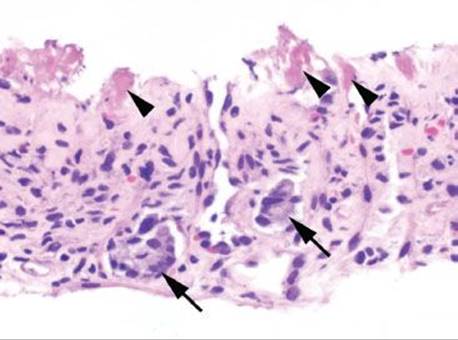

Figure 4.53 Ischemic colitis pattern, early. Lamina propria hemorrhage (arrowheads) is present.

Figure 4.54 Ischemic colitis pattern, withered crypts. Crypt epithelium becomes damaged and sloughs, giving a “withered” appearance to the crypts (arrowheads). Compare these withered crypts to the right side of the photo, which are better preserved.